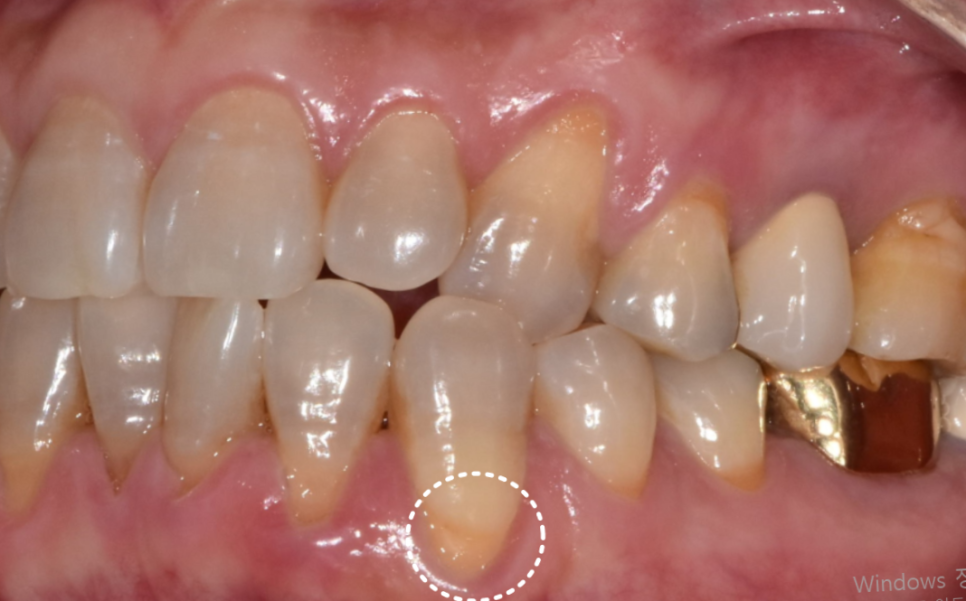

자는 동안 이를 꽉 물거나 가는 것,

비정상적인 교합 문제가 있으면

치아와 잇몸뼈에는 계속해서 과한 힘이 전달됩니다.

이 힘이 반복되면 잇몸뼈에 미세한 손상이 쌓이게 되고,

어느 순간부터는 뼈의 양이 줄어들면서

그 뼈를 덮고 있던 잇몸도 함께 뒤로 물러나게 됩니다.

송곳니 쪽만 반대교합으로 인해 잇몸이 내려앉고 치아가 길어 보이는 상태

그로 인해, 유달리 힘을 많이 받는 치아는

더 길어 보일 수 있습니다.